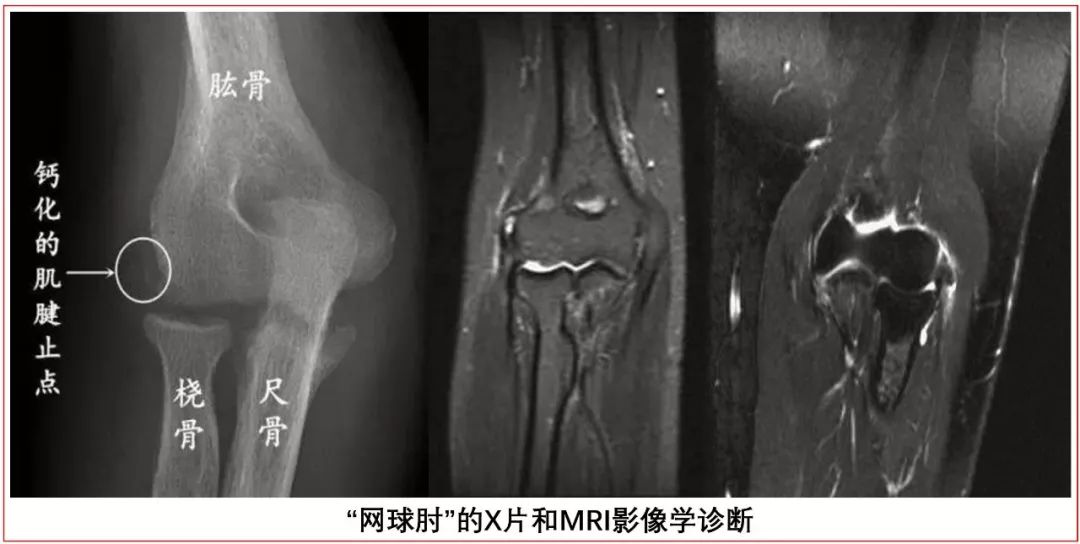

主要诊断依靠体格检查,影像学检查只能辅助诊断。早期网球肘X片往往正常,慢性“网球肘”有时可见到桡侧腕短肌肌腱钙化表现;B超检查可发现肌腱的结构变化(例如增厚、变薄、变性和肌腱撕裂等);MRI检查可辅助支持诊断,因其费用昂贵,一般不作为常规。